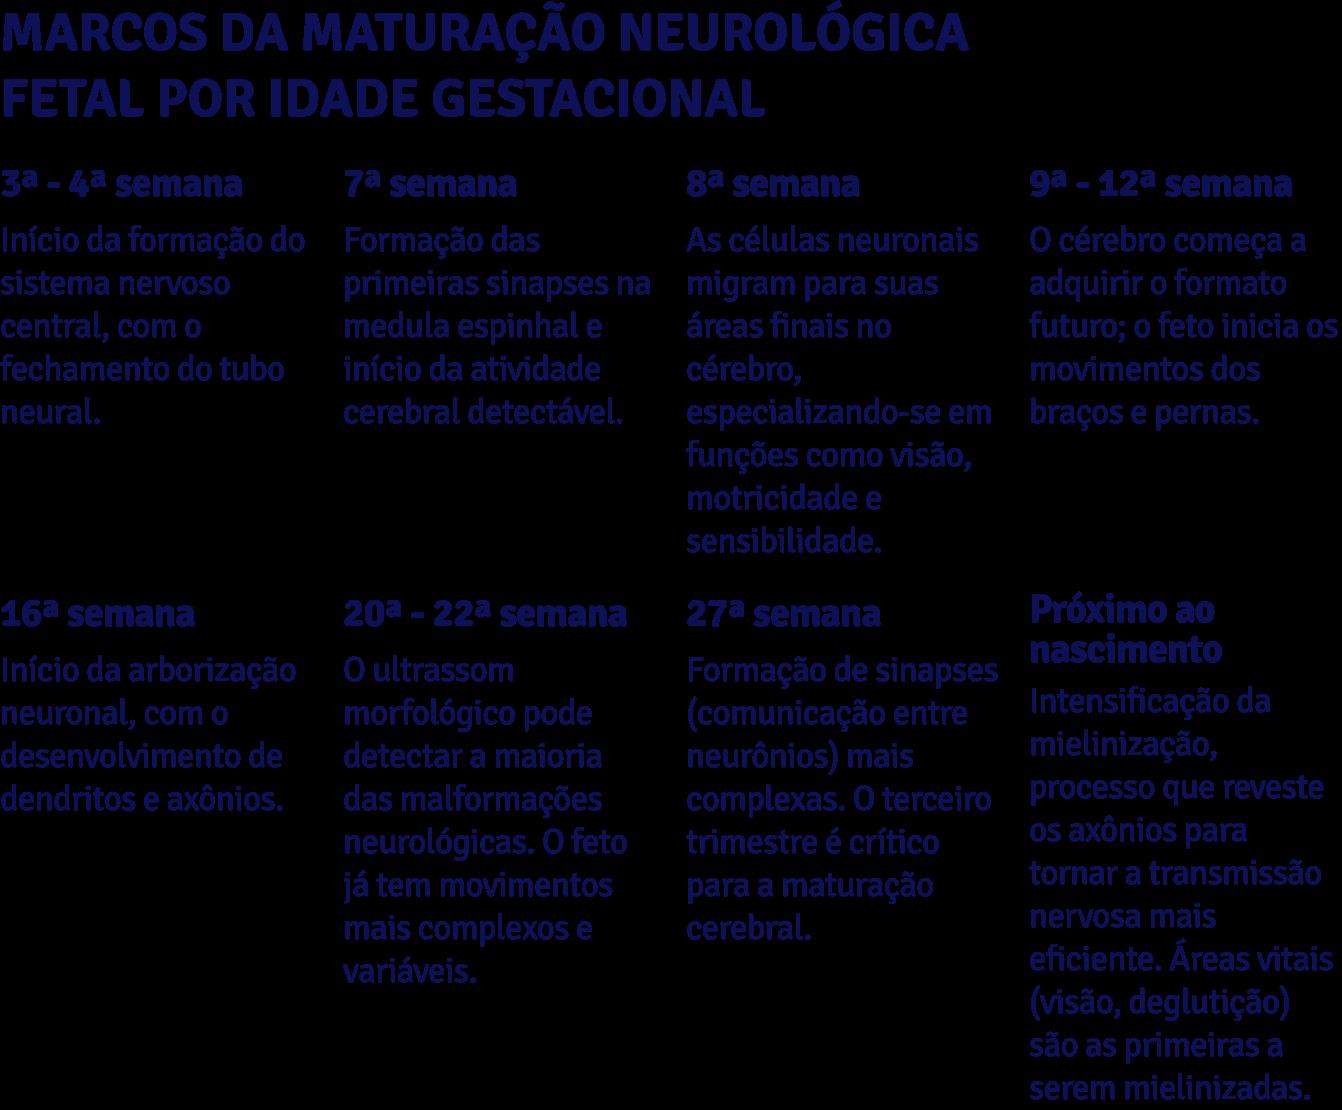

Do ponto de vista do neurodesenvolvimento, a prematuridade representa uma interrupção abrupta, em diferentes etapas e intensidade, da maturação cerebral intrauterina. O período final da gestação é marcado por processos intensos de mielinização, sinaptogêneses e organização cortical. Quando o nascimento ocorre precocemente,

esses processos podem ser alterados porque continuam ocorrendo em um ambiente hospitalar, muitas vezes estressante (SILVA et al., 2024; JAHN; GERZSON; ALMEIDA, 2021).

A interrupção precoce da gestação interrompe processos fundamentais da maturação neurológica, como a migração neuronal, mielinização e organização sináptica. Essas alterações explicam,

em parte, o perfil funcional frequentemente observado: hipotonia, lentidão de processamento, dificuldades de atenção, regulação sensorial alterada e atrasos na aquisição de marcos motores, cognitivos e de linguagem.